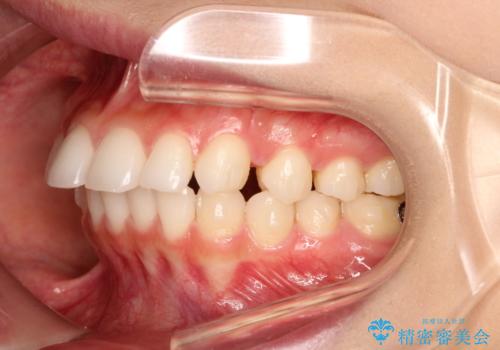

出っ歯の矯正治療 歯を抜かずにインビザラインで

- インビザラインで出っ歯を治したいとの希望がありました。

上顎の歯を全体的に後方に移動させて前歯を引っ込める計画としました。

インビザラインで目立たずに、痛みも少なく矯正治療を終えることができ満足していただけました。